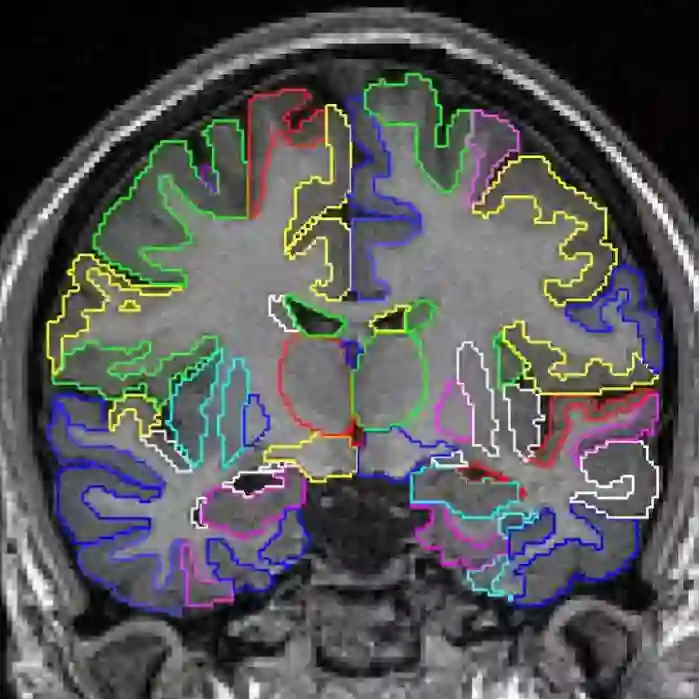

3、Data augmentation using learned transformations for one-shot medical image segmentation(利用学习变换进行数据增强,实现one-shot医学图像分割)

作者:Amy Zhao, Guha Balakrishnan, Frédo Durand, John V. Guttag, Adrian V. Dalca

摘要:图像分割是医学应用中的一个重要课题。基于卷积神经网络的方法获得了最先进的精度;然而,它们通常依赖于带有大型标记数据集的监督训练。医学图像的标注需要大量的专业知识和时间,而典型的手工调优的数据增强方法无法捕捉这些图像中的复杂变化。我们提出了一种自动数据增强方法来合成标记医学图像。我们在分割磁共振成像(MRI)脑扫描的任务中展示了我们的方法。我们的方法只需要一次分段扫描,并利用半监督方法中的其他未标记扫描。我们从图像中学习转换模型,并使用该模型和带标记的示例来合成其他带标记的示例。每个转换都由空间变形场和强度变化组成,从而能够综合复杂的效果,如解剖学和图像采集过程的变化。我们展示了使用这些新示例训练有监督的分割器,对于one-shot生物医学图像分割的最先进方法有着显着的改进。我们的代码可以在https://github.com/xamyzhao/brainstorm上找到。